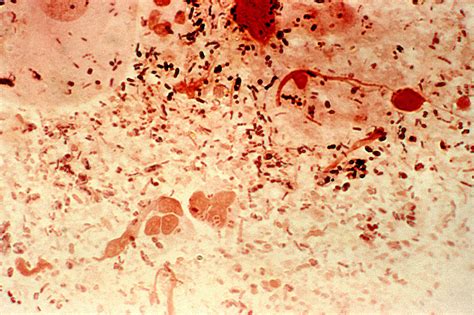

Diplococci Gram Negative Bacteria are spherical bacteria that typically appear in pairs. The term "diplococci" refers to their arrangement in pairs, while "Gram negative" indicates their staining properties. When subjected to the Gram staining procedure, these bacteria do not retain the crystal violet dye and appear pink or red under a microscope. This characteristic is due to their thin peptidoglycan layer and the presence of an outer membrane.

• Gram Staining: They do not retain the crystal violet dye during the Gram staining process, appearing pink or red.